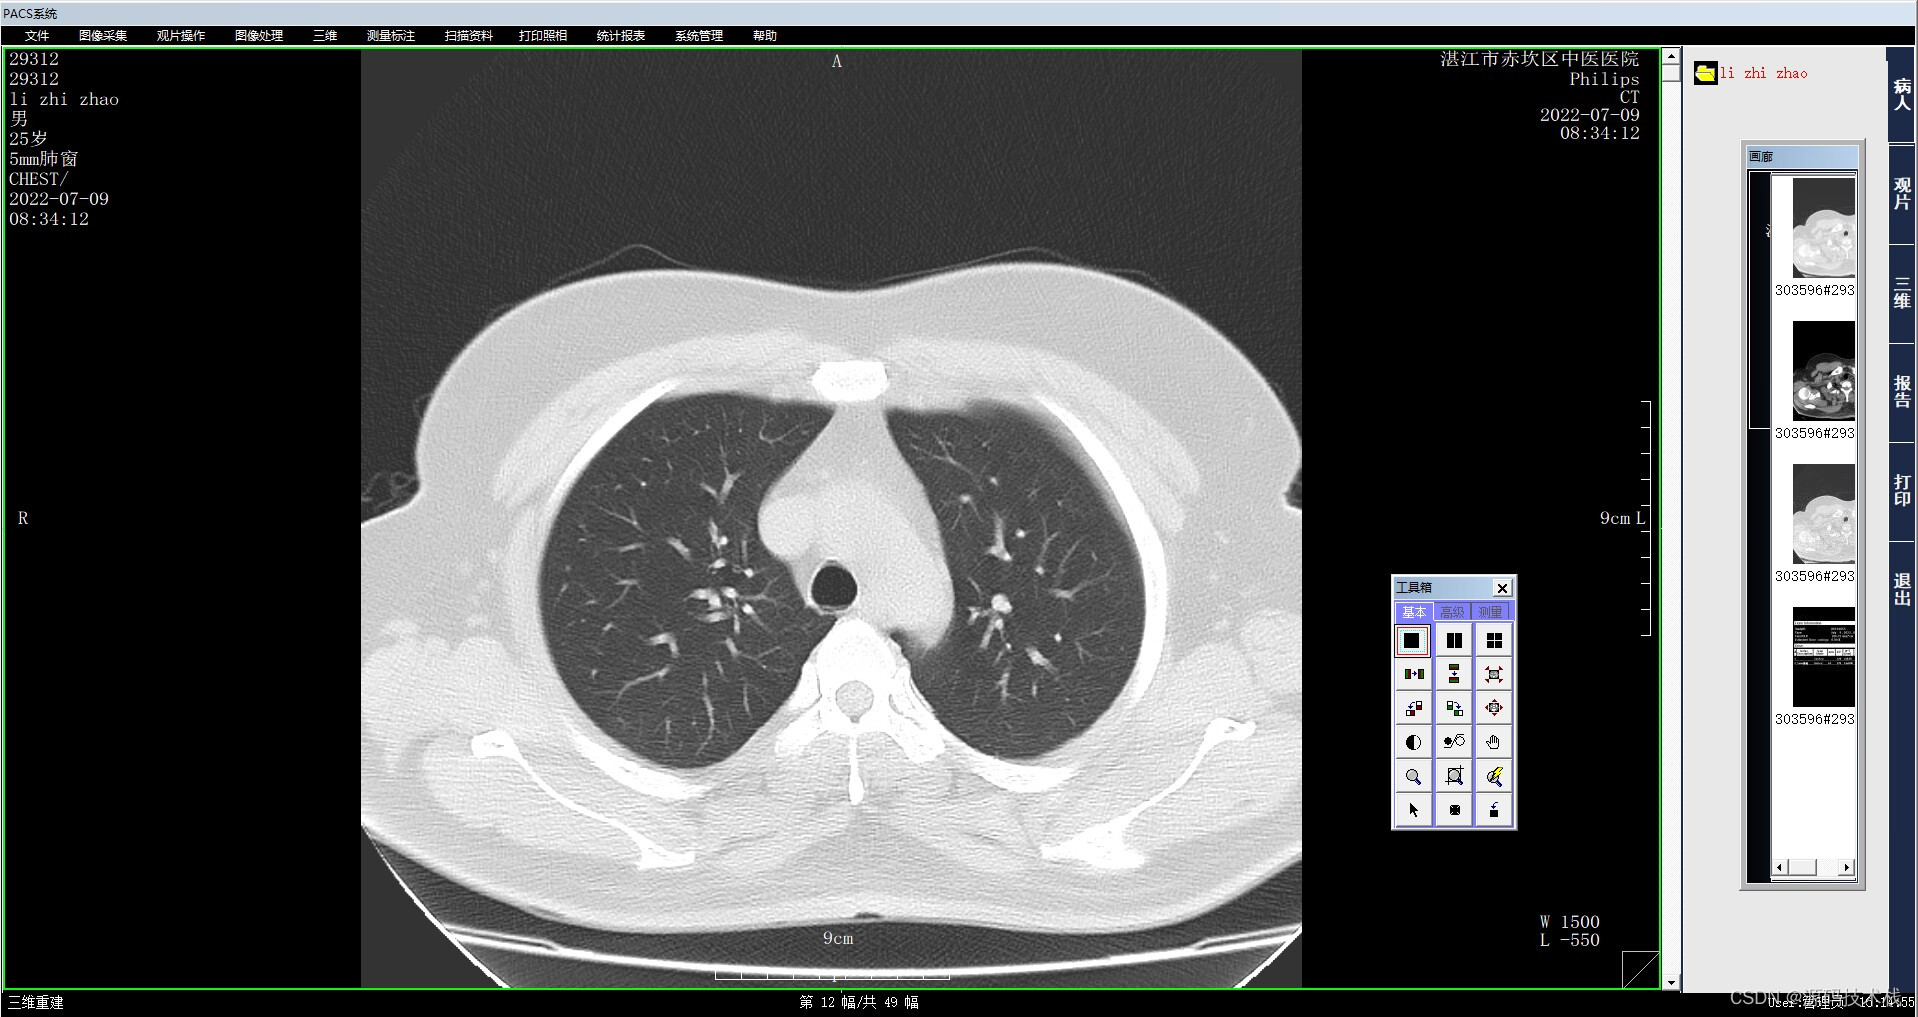

1、MPR

MPR(Multi-Planar Reformatting),多平面重建,是将扫描范围内所有的轴位图像叠加起来再对某些标线标定的重组线所指定的组织进行冠状、矢状位、任意角度斜位图像重组。MPR适用于任一平面的结构成像,以任意角度观察正常组织器官或病变,可以显示腔性结构的横截面以观察腔隙的狭窄程度、评价血管受侵情况、真实地反映器官间的位置关系等。

优点:

a. 能任意产生新的断层图像,而无需重复扫描

b. 原图像的密度

值被忠实保持到了结果图像上

c. 曲面重组能在一幅图像里展开显示弯曲物体的全长。

缺点:

a. 难以表达复杂的空间结构

b. 曲面重组易造成假阳性。